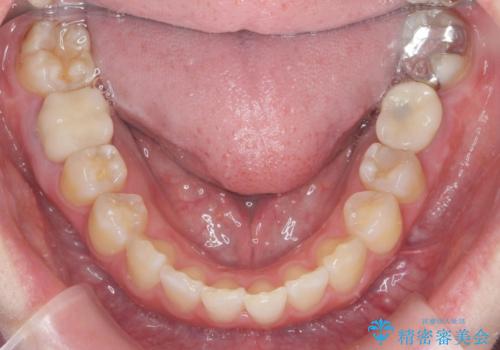

ねじれた前歯を改善するマウスピース矯正

- 大きくねじれた前歯をまっすぐに並べたい。と矯正治療を希望され来院されました。

前歯をきっちり並べるには奥歯の噛み合わせの調整を行い上下の前後的関係を治し、ねじれを取るスペースを確保していきます。

当初前歯だけ治れば良い、という心算で来院されましたが奥歯の噛み合わせも負担が大きく問題の起きやすいことをお伝えし上顎の奥歯をきっちりと後方移動行い噛み合わせの調整を行いました。・